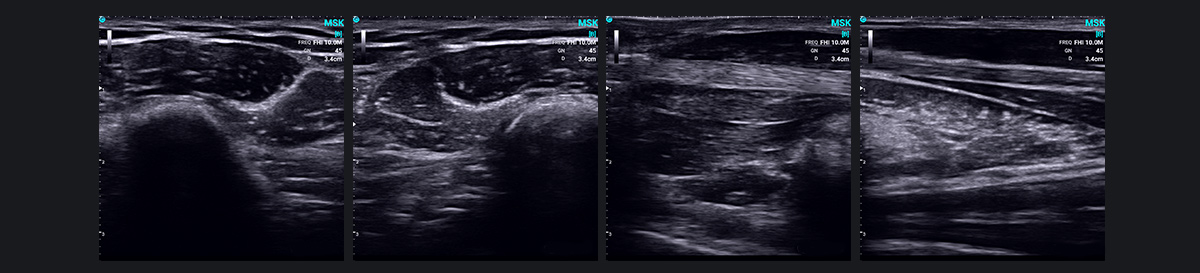

肌肉骨骼超声(MSK)近年来已成为一项突破性技术,利用高频超声来诊断肌肉骨骼系统疾病。它提供肌肉、肌腱、韧带、周围神经和其他浅表软组织结构的清晰图像,识别炎症、肿瘤、损伤和畸形等状况。

MSK 超声波在诊断关节疾病方面特别有效,包括类风湿性关节炎和痛风性关节炎。它还有助于检测代谢和全身疾病以及相关的关节病,提供各种病症的全面视图。

此外,超声波的实时动态成像功能可以检测和观察仅在运动期间或特定位置出现的异常或病变,例如肌腱和神经脱位或肩部撞击综合症。它还可以同时扫描受影响的一侧和健康的一侧,从而有助于动态比较组织结构以识别异常情况。